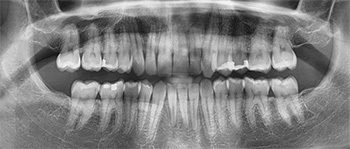

The patient completed treatment in seven and a half months with normalized overbite and resolved crowding in both arches (Figs. 9–10). Improvement of distal root tip of the LR1 may have been possible had I added a vertical attachment. No refinements were needed, which was critical for this patient’s treatment timeline. The patient reported high satisfaction because of the convenience of remote monitoring and minimal in-office visits.

Summary of treatment metrics:

• Number of stages: 30

• Refinements: 0

• Treatment duration: 7.5 months

• Polymer selected: FXClear

• Remote monitoring: FXOnTrack

• Treatment visits: Four total